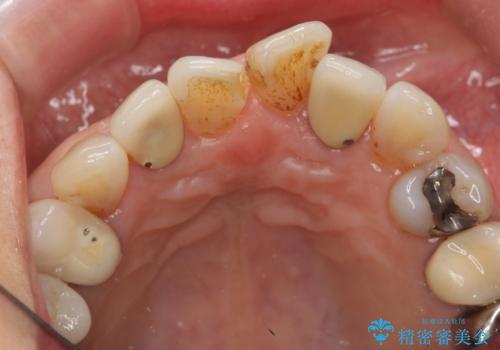

左上の前歯のみねじれが大きいため、歯の位置をひっこめたかぶせものにするために、神経の治療を行っています。

- 59.5万円 (オフィスホワイトニング 3万円、ジルコニアクラウン スタンダード 10万円×4本、仮歯 1万円×4本、精密根管治療(左上1)6万円×1本、ファイバーコア 2万円×1本)費用は治療当時の料金となります